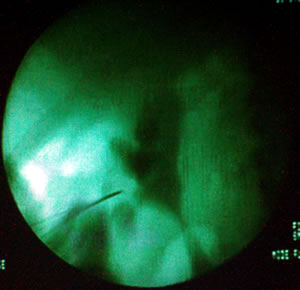

Профессор предпочитает проводить пункцию под контролем

рентгена, а не под контролем УЗИ, считает, что это позволяет

иметь стереоскопическую картину.

Алексей Георгиевич начал операцию с пункции лоханки через

нижнюю чашечку пункционной иглой под контролем рентгена.

Лоханка при проведении пункции контрастирована по меточнику.